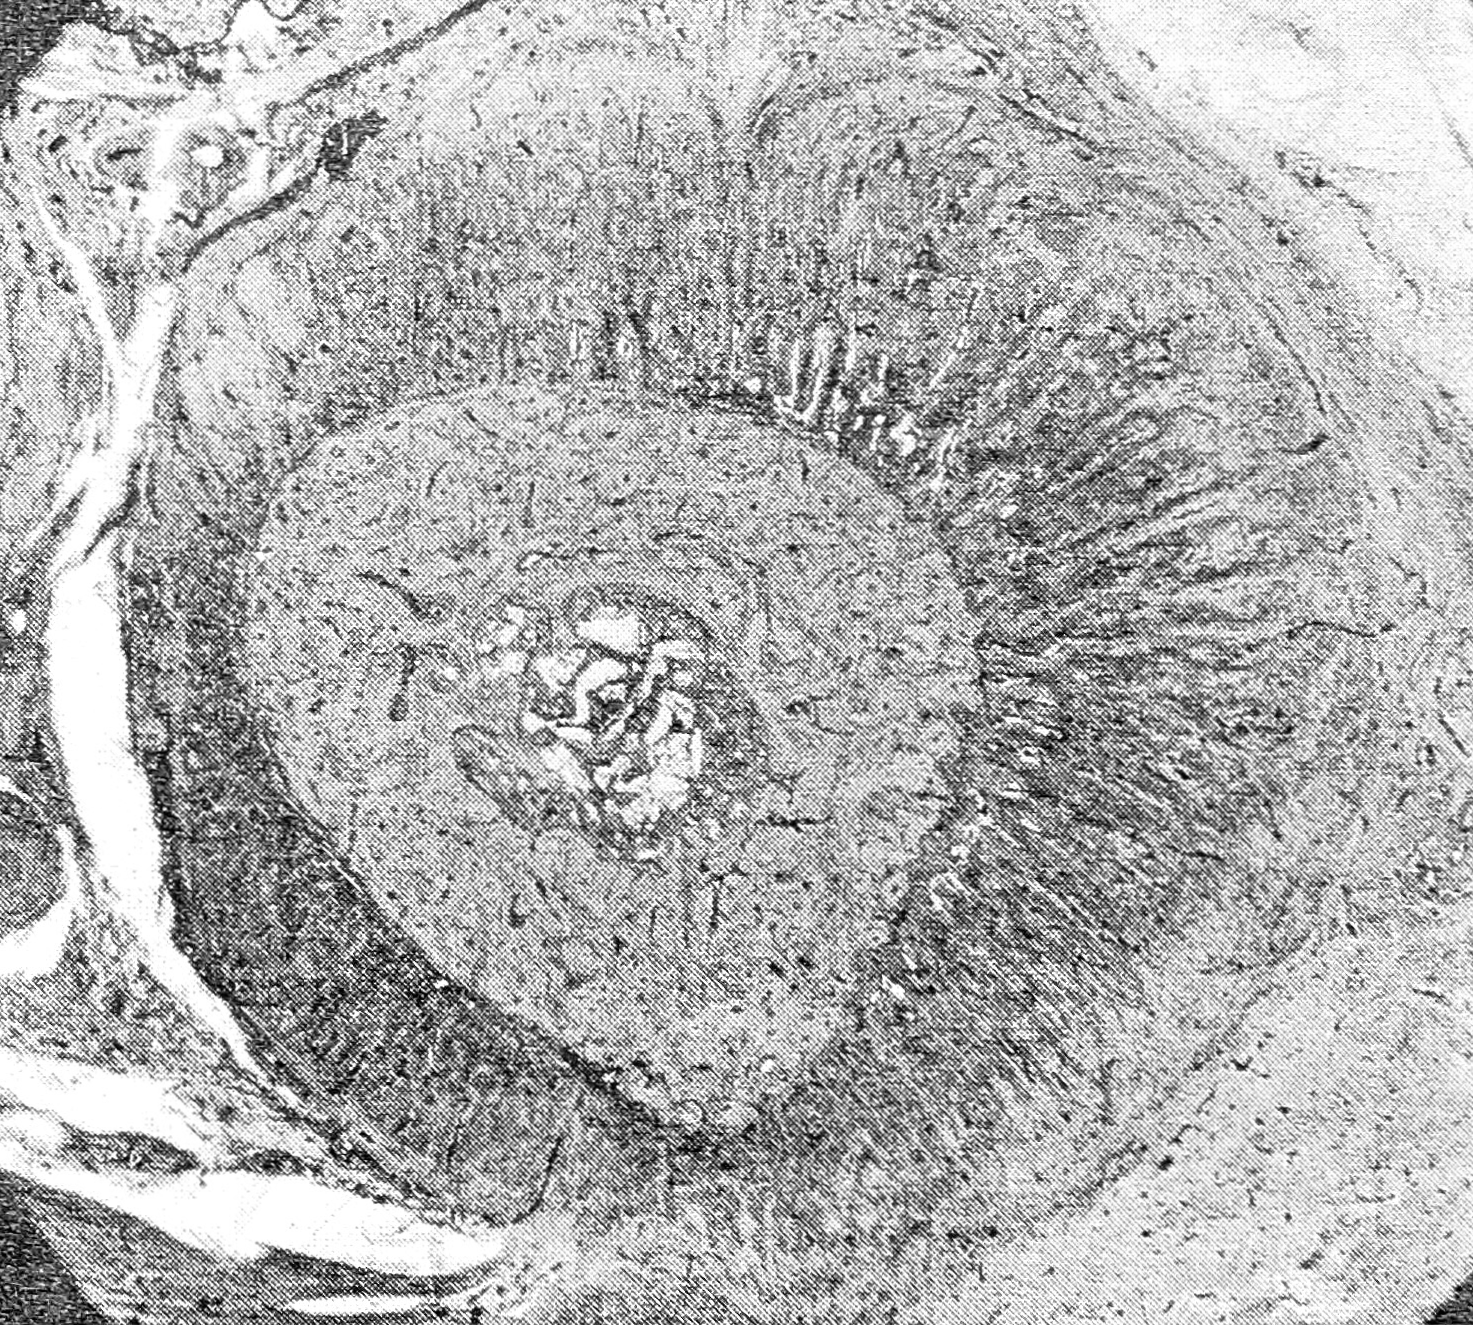

Рис. 5. Свежий новообразованный участок щели и участок, заполненный фиброзной соединительной тканью (85-е сутки со дня возникновения ползучего перелома).

Окраска гематоксилином и эозином. Ув. 80.